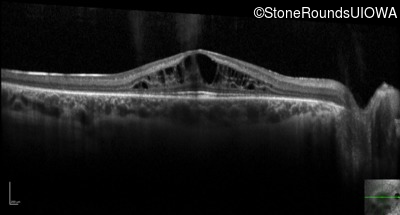

Optical Coherence Tomography - Right - 20/40 -1

Exemplar / OCT Stack